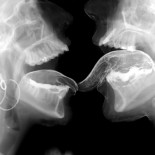

España, dispuesta a participar en el escudo antimisiles de la OTAN

La participación española pasará, según fuentes militares, por la base naval de Rota, aunque de momento se desconocen los detalles concretos del dispositivo. En cualquier caso las capacidades españolas antimisiles se concentran en las fragatas F100 y en el regimiento de artillería antiaérea 74.